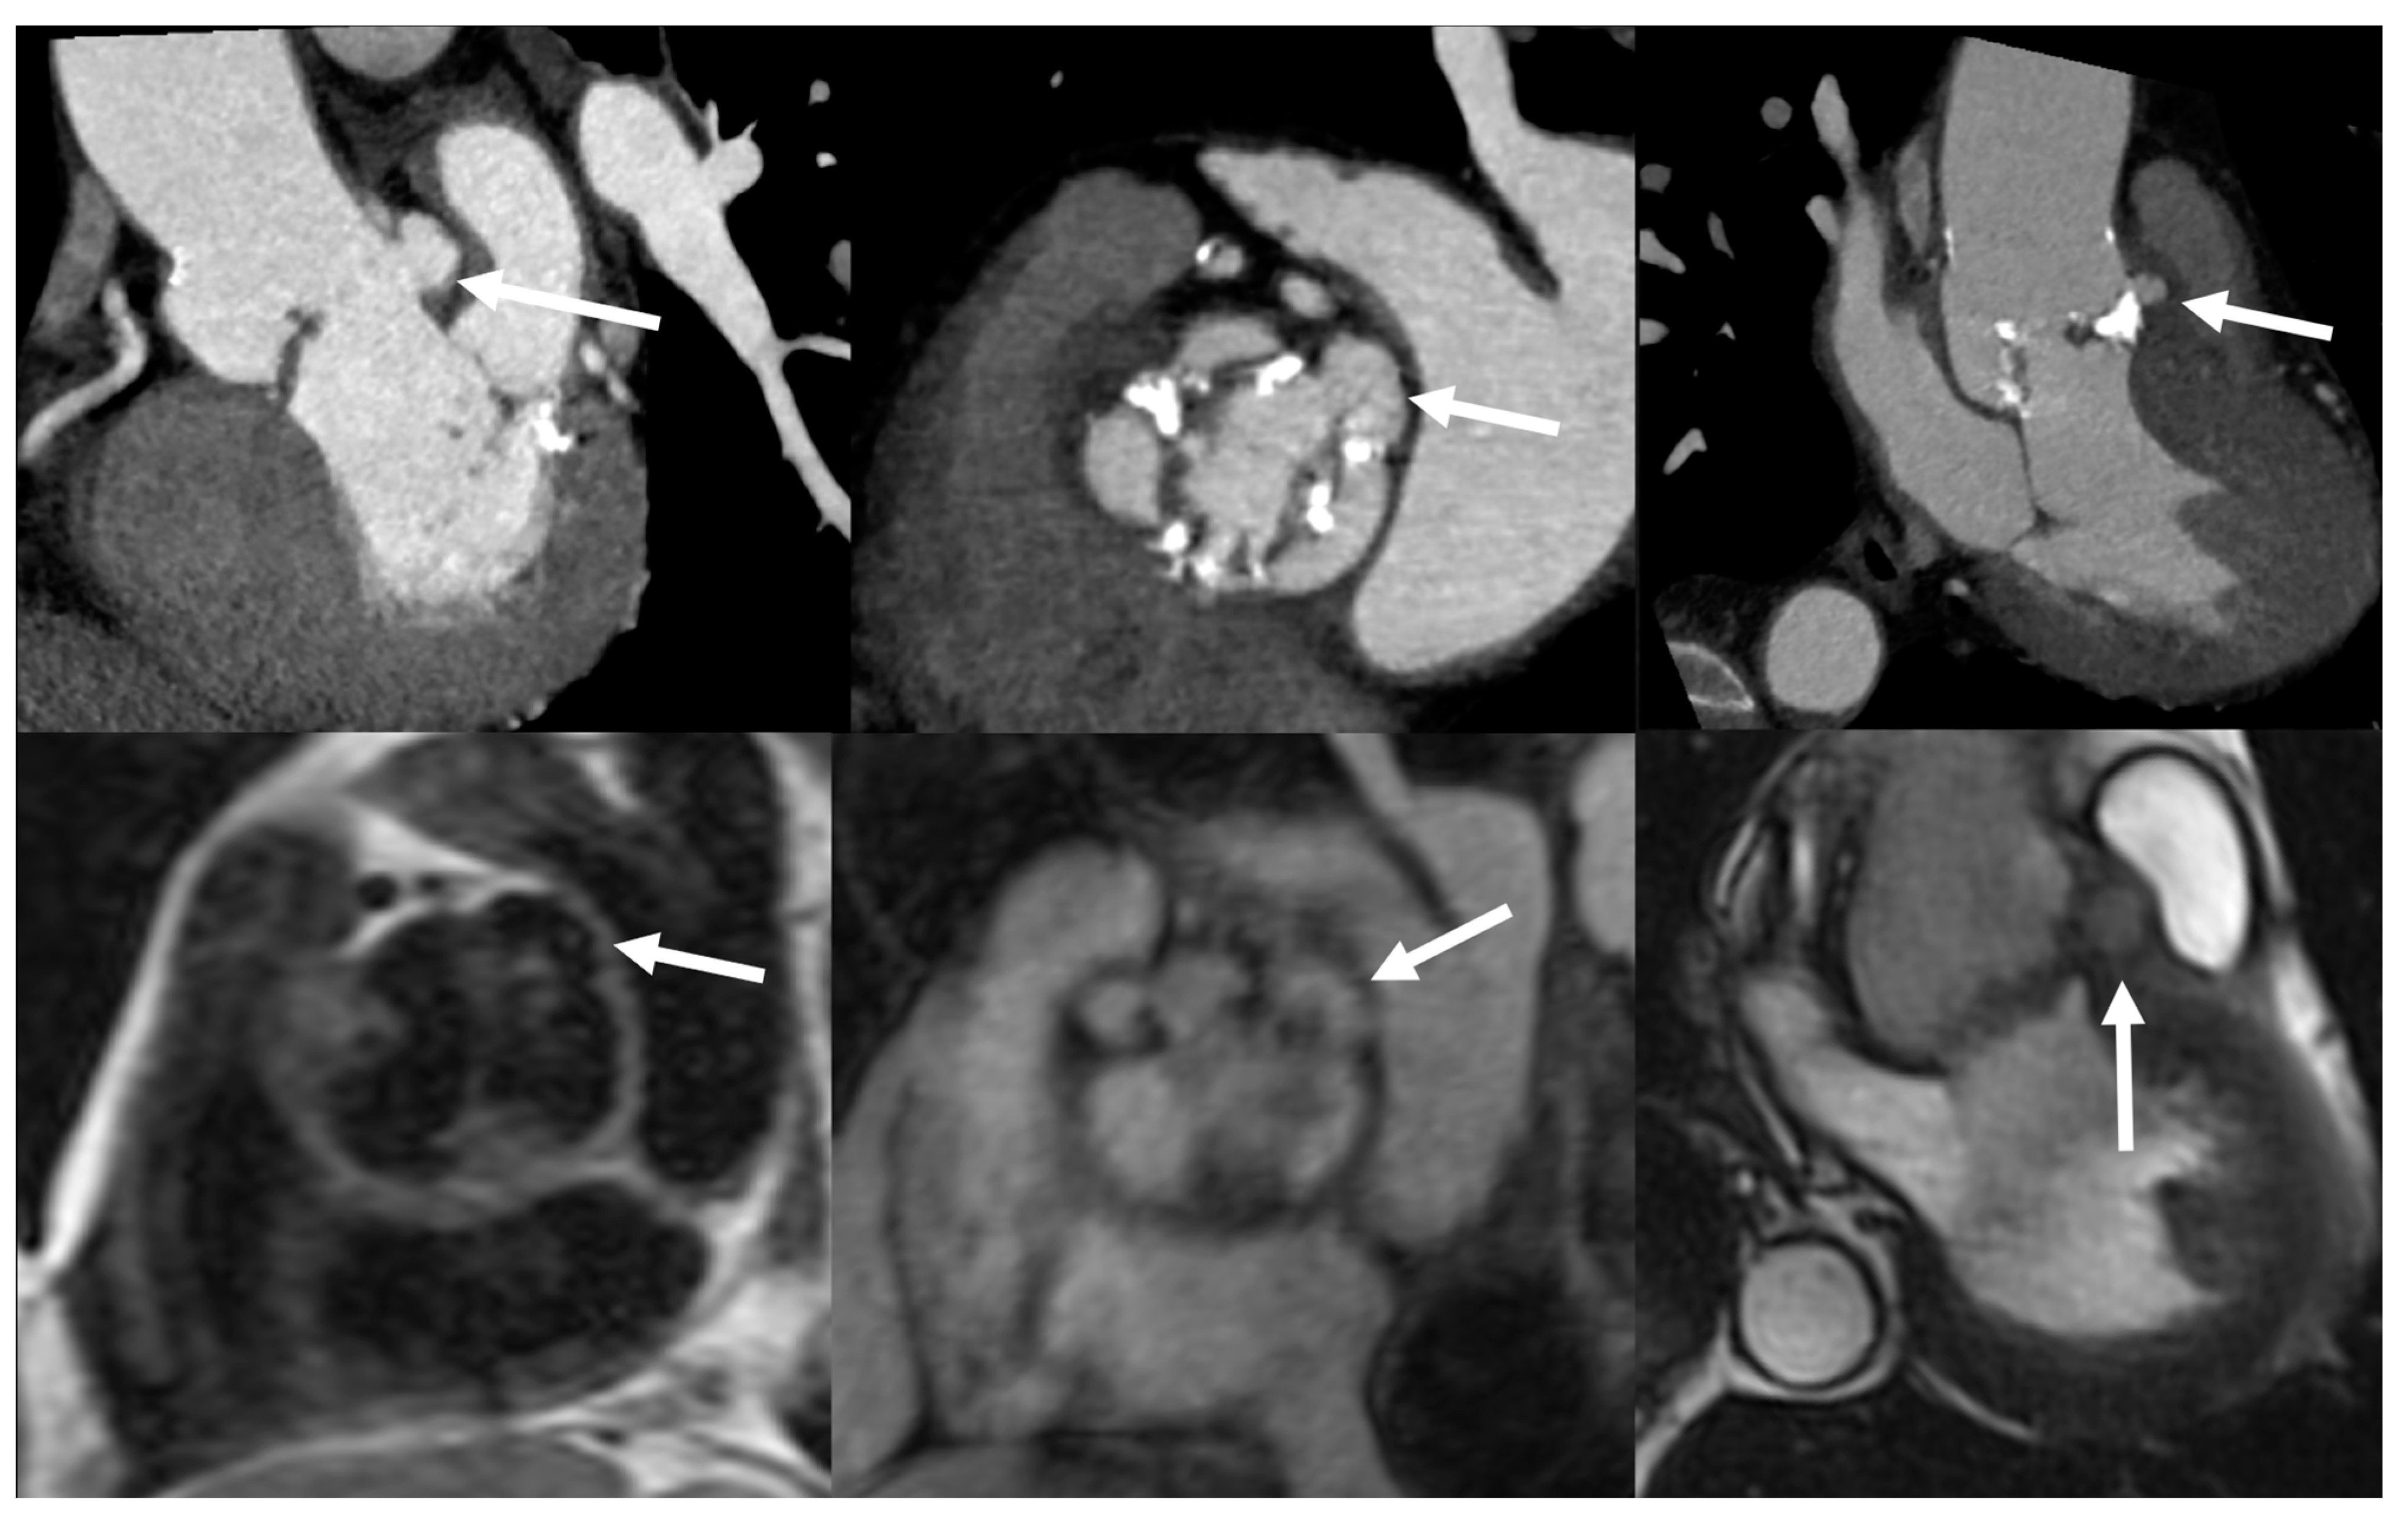

4.3. Role of CCTA in Diagnosing IE and Local Complications

6.3. Role of CCTA in Diagnosing PVE and Local Complication

6.6. Role of CMR in Diagnosing PVE and Local Complications

| Left-sided IE | Good visualization of mitral and aortic valve. Valvular dysfuction assessment. Identification of complication (i.e., valvular regurgitation). | Difficult differential diagnosis in presence of marantic vegetations or high calcification. | Detection of vegetations and valve perforation. Assessment of perivalvular extent of disease (abscesses, pseudoaneursysm, fistula). | Inferior to TTE/TOE in detecting small vegetations (<2 mm). | Prognostic assessment: simultaneous detection of embolism, metastatic lesions and portal of entry. | Limited sensitivity for small vegetations. | Evaluation of distant emboli and portal of entry. | Limited role because of low sensitivity for small vegetations. | Capability to assess vegetations (inferior to TTE/TOE). Capability to assess local complications. Independent by acoustic window. May detect concomitant myocardial inflammation. | Not included in current guidelines for IE diagnosis. |

| PVE | Routinely used for follow up; it allows sequential assessment of prosthesis function. TOE is often required to correctly assess the prosthesis. | Limited by prosthetic material artifacts (i.e., acoustic shadow). Early complication (i.e., abscess) can be difficult to identify. | Identification of complications (paravalvular leakage, abscesses, pseudoaneurysm, dehiscence, and extension to adjacent structures). Capability to visualize large vegetations (>10 mm). | Low image quality for beam hardening artifacts. Limited in assessing small vegetations (<4 mm). | High diagnostic accuracy. Good assessment of perivalvular/periprosthetic complications. Reduction of rate of misdiagnosed PVE. Role in prediction of MACEs. Prognostic significance. | Host reaction may reduce specificity (risk of false-positive studies until 3 months after surgery). | High specificity for infection. Reduction of rate of misdiagnosed PVE. Differential diagnosis between septic and sterile vegetations. | Limited sensitivity for small lesions. | Image quality severely hampered by susceptibility artifacts (especially from mechanical prostheses). | |